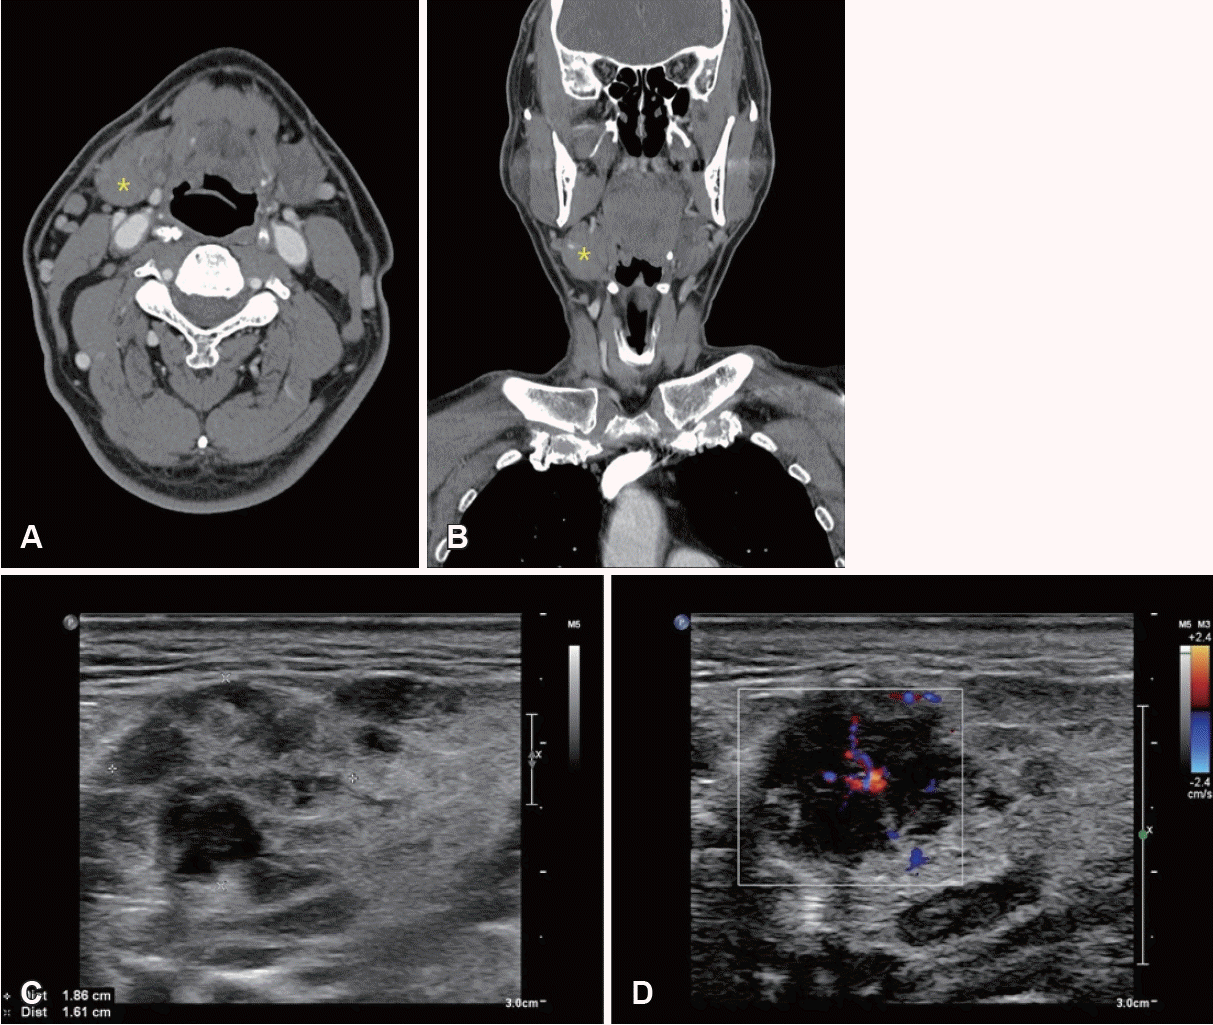

Fig. 1.

Radiologic and ultrasonic findings of patient case 1. A and B: Enhanced axial and coronal images of salivary gland CT scan show slightly enlarged to normal right submandibular gland (asterisk). C and D: Multicystic and hypervascular right submandibular gland on ultrasonography.